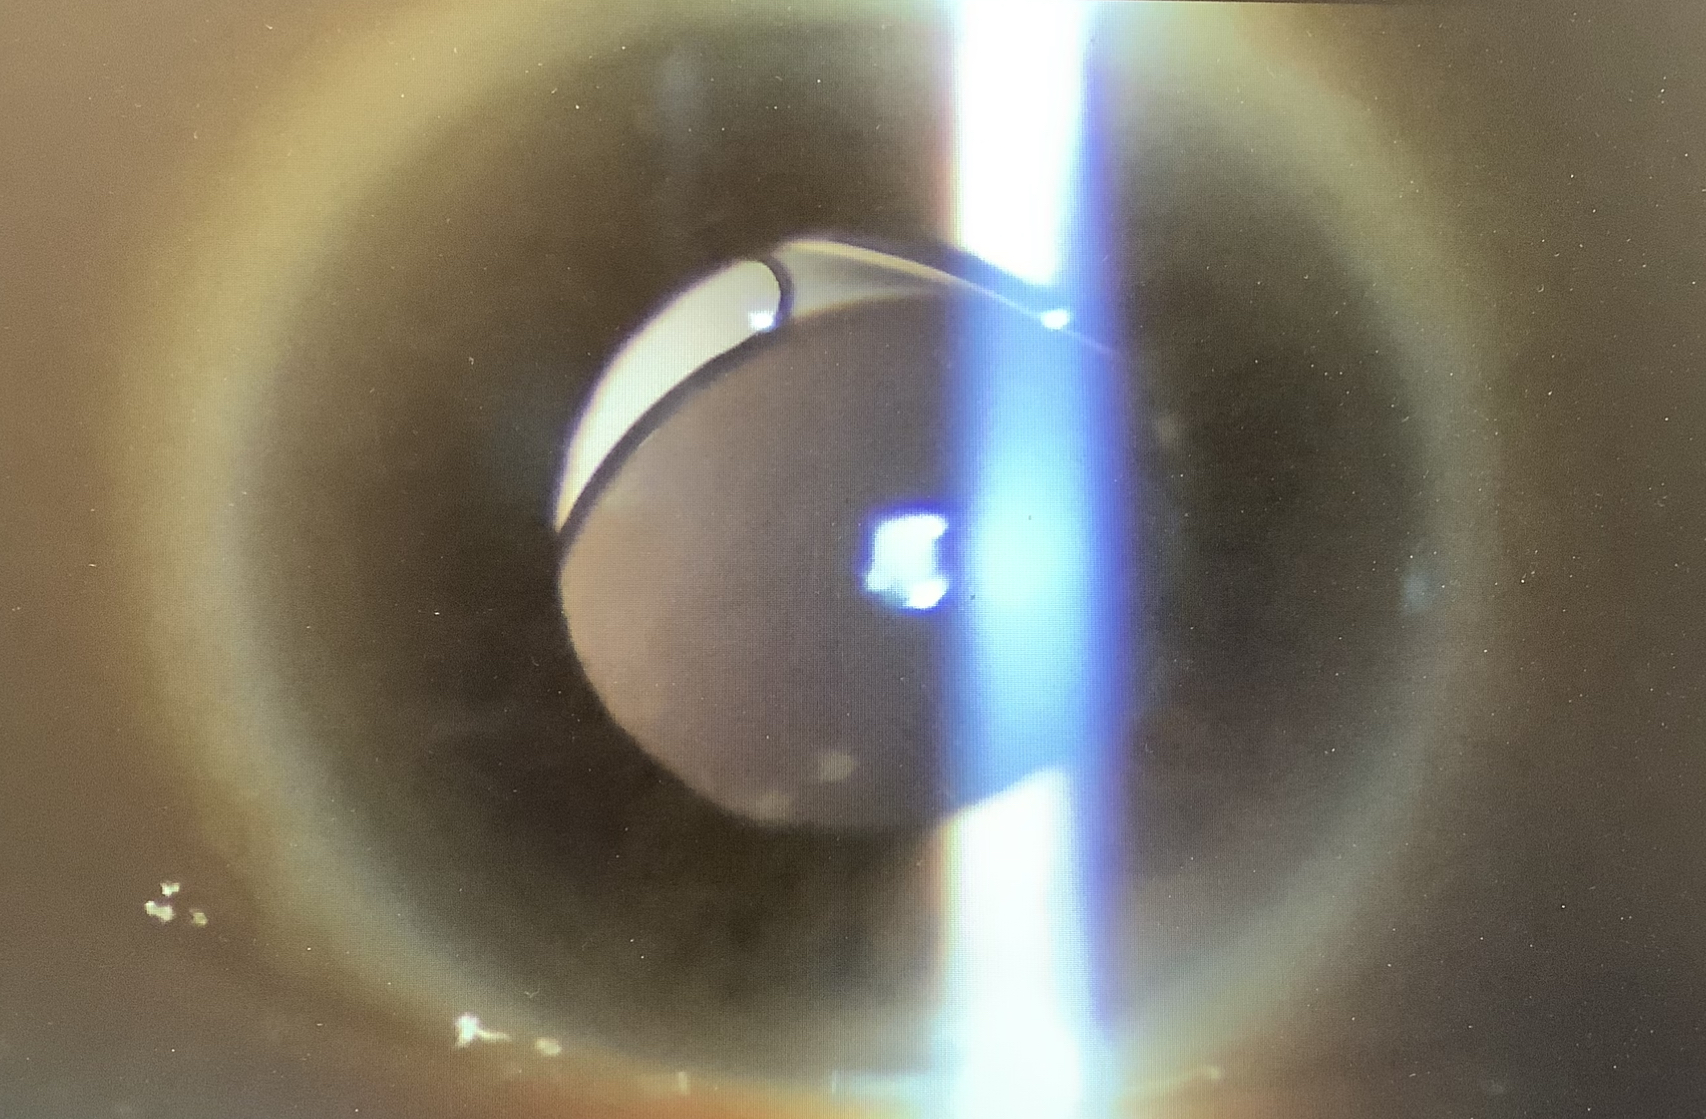

実際、眼内レンズに若干の偏りが見られ、おそらく、レンズを眼の壁に縫った糸の片方が外れ、宙ぶらりんで、体を起こしている時はそれなりの位置にあるのですが、横になると、パタンと眼の奥の方に落ち込んでしまう状態と思われました。

こうなると、レンズを取り出して、新たなたレンズを眼の壁に固定する手術(眼内レンズ強膜内固定)が必要なので、レンズが完全に眼の奥に落ち込まない内に少し早めに手術を予定させていただきました。(完全に落ちてしまっても手術は可能ですが、ちょっと一手間かかるので、早めがよいかと思いました、、、)